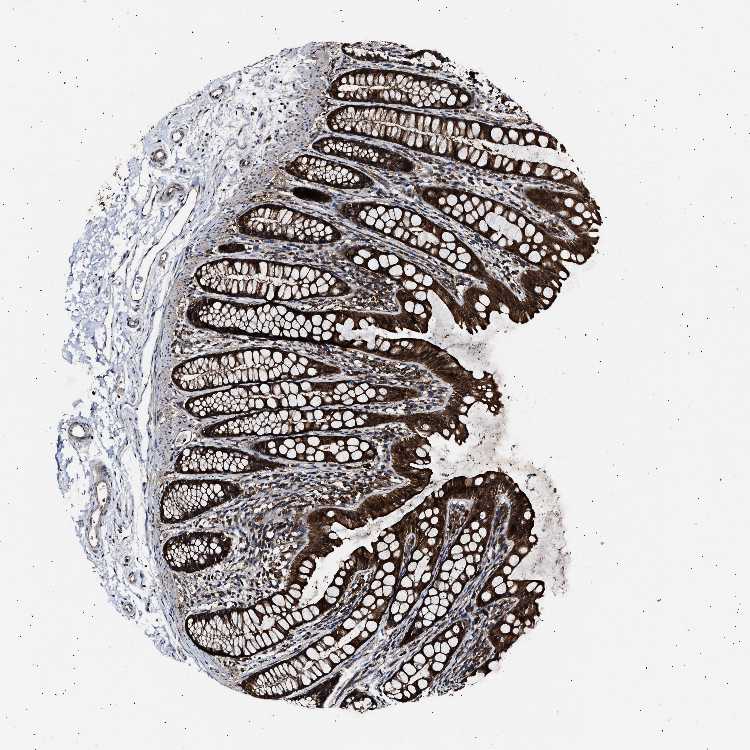

CCT8